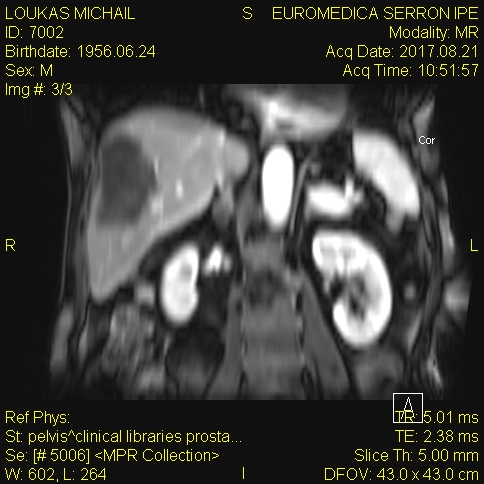

Polycystic liver disease. Red arrow. Infected hepatic cyst (Courtesy Dr. V. Penopoulos)